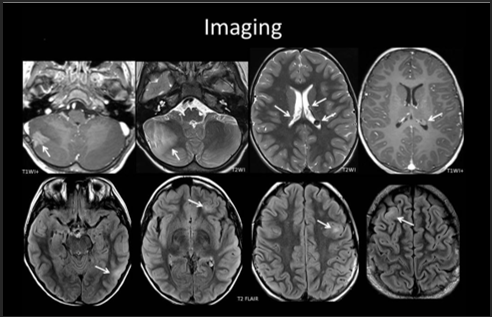

A 3-year-old child is admitted to the hospital due to decreased appetite and weight loss. She has been afebrile, and has not had vomiting or diarrhea.

Her activity level has decreased over the past two weeks.

She had been healthy until 2 months ago, when she was hospitalized for 48 ...

infection with mild respiratory distress and poor fluid intake.